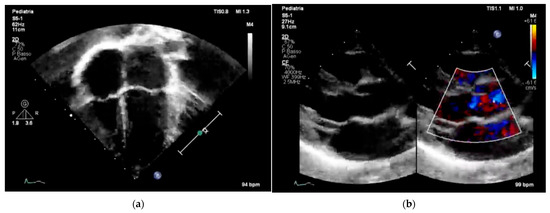

Figure 3 and Figure 4 underscore the importance of age-specific interpretation in pediatric cardiology to distinguish normal developmental findings from true abnormalities.

These representative images highlight the importance of pediatric-specific expertise in interpreting both echocardiograms and electrocardiograms. In children, normal anatomical and electrophysiological features change with age, and misreading them can lead to overdiagnosis or unnecessary restrictions on physical activity. Additionally, including color Doppler imaging in echocardiography (Figure 3b) emphasizes the importance of evaluating hemodynamic function alongside structural integrity, especially in screening protocols designed for early detection of CHD [7] or functional issues. Similarly, the ECG patterns shown in Figure 4b display the typical pattern of physiological T-wave inversion in the right precordial leads (V1–V3), which is common in children under 8 years old. This underscores the need for age-specific ECG interpretation criteria to prevent normal variants from being mistaken for pathological conditions.

Overall, Figure 3 and Figure 4 emphasize the importance of combining imaging and electrophysiological tools in pediatric cardiovascular screening while also highlighting the crucial role of age-specific norms and clinical context in ensuring accurate, efficient, and cost-effective screening results.

Figure 3. Two representative examples of echocardiography in pediatric subjects: (a) four-chamber pediatric view with apex down in 6-year-old children; (b) parasternal long axis view of a 6-year-old child; black and white on the left and color Doppler flow on the right.